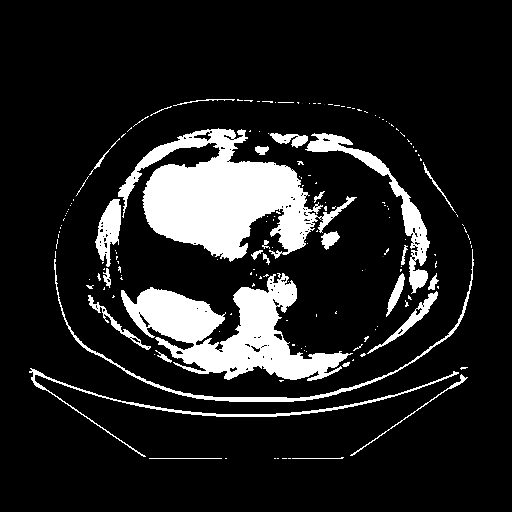

Generated VENOUS CT scan (A→B translation)

Full window (WL 1023.5, WW 4095 β†’ Low βˆ’1024, High +3071)

Actual HU range: [-1024.0, 3071.0]